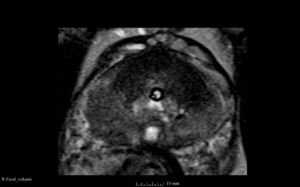

We used this sample data with Reader 1 segmentations to visually evaluate differences in the registration results. All three results of BRAINSFit with ITKv3 in Slicer 3.6 look reasonable. Using BRAINSFit with ITKv4 in Slicer 4.4 creates a reasonable result for Case 7, but look strongly distorted towards the edges of the bounding box in Case 8 and 9.

Case 8

Reference intraop volume

Reg Result Slicer 3.6 with ITKv3

Reg Result Slicer 4.4 with ITKv4